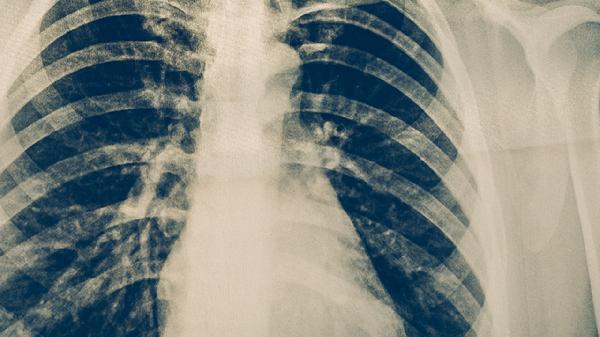

吸入性肺炎患者除药物治疗外,需保持半卧位减少误吸风险,进食时注意细嚼慢咽。出现发热、咳嗽加剧或呼吸困难时应及时复诊,避免自行调整用药方案。康复期可进行呼吸训练增强肺功能,保证充足营养摄入但需控制进食速度,定期随访胸部影像学评估治疗效果。